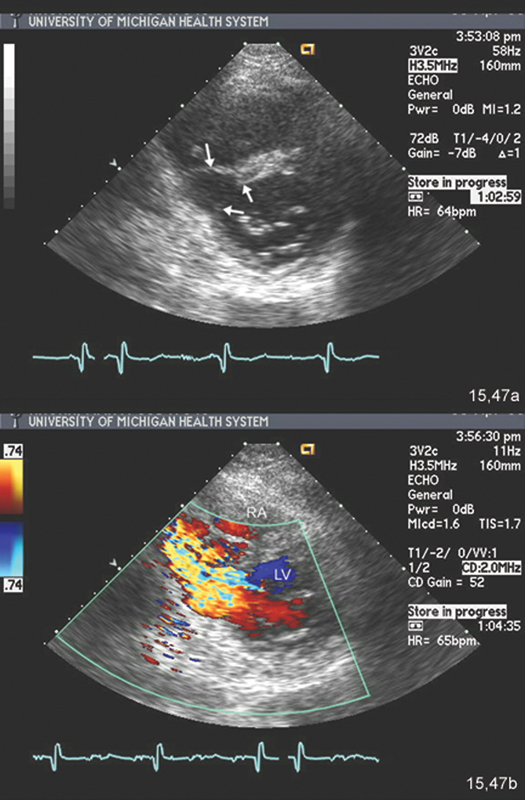

فحوصات تشخيصية لبعض امراض القلب والشرايين التاجية